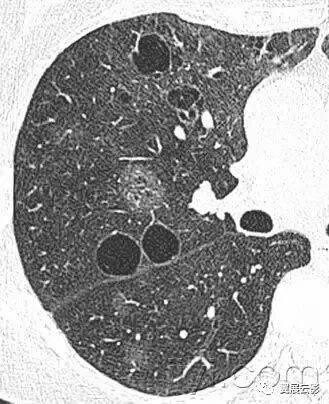

十八、小叶中心性:

解剖:小叶中心性用于描述次级肺小叶的支气管血管束中心区域。病理学上也用这一术语描述终末小支气管远端,位于呼吸性细支气管和肺泡管中心的病变。

CT:正常次级肺小叶中心的点状或者线状的密度增高影,胸膜下25px范围内最明显,代表小叶内的动脉,直径约1mm。

小叶中心性异常包括(1)结节(2)树芽征,提示小气道病变(3)由于临近间质的增厚或者浸润导致小叶中心结果更加清晰(4)小叶中心性肺气肿导致的异常低密度。

附图为小叶中心性肺气肿